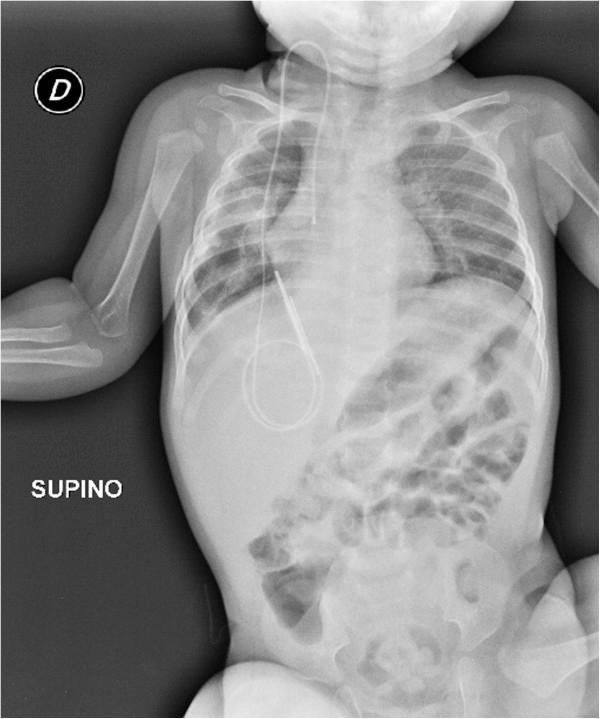

We describe the case of a 7-month-old female baby of Italian mother and Kurdish father who was diagnosed with type III pleuropulmonary blastoma, which entirely occupied her right hemithorax.

我们描述了一名7个月大女婴的病例,其母亲为意大利人,父亲为库尔德人,被诊断为III型胸膜肺母细胞瘤,肿瘤完全占据了她的右半胸。